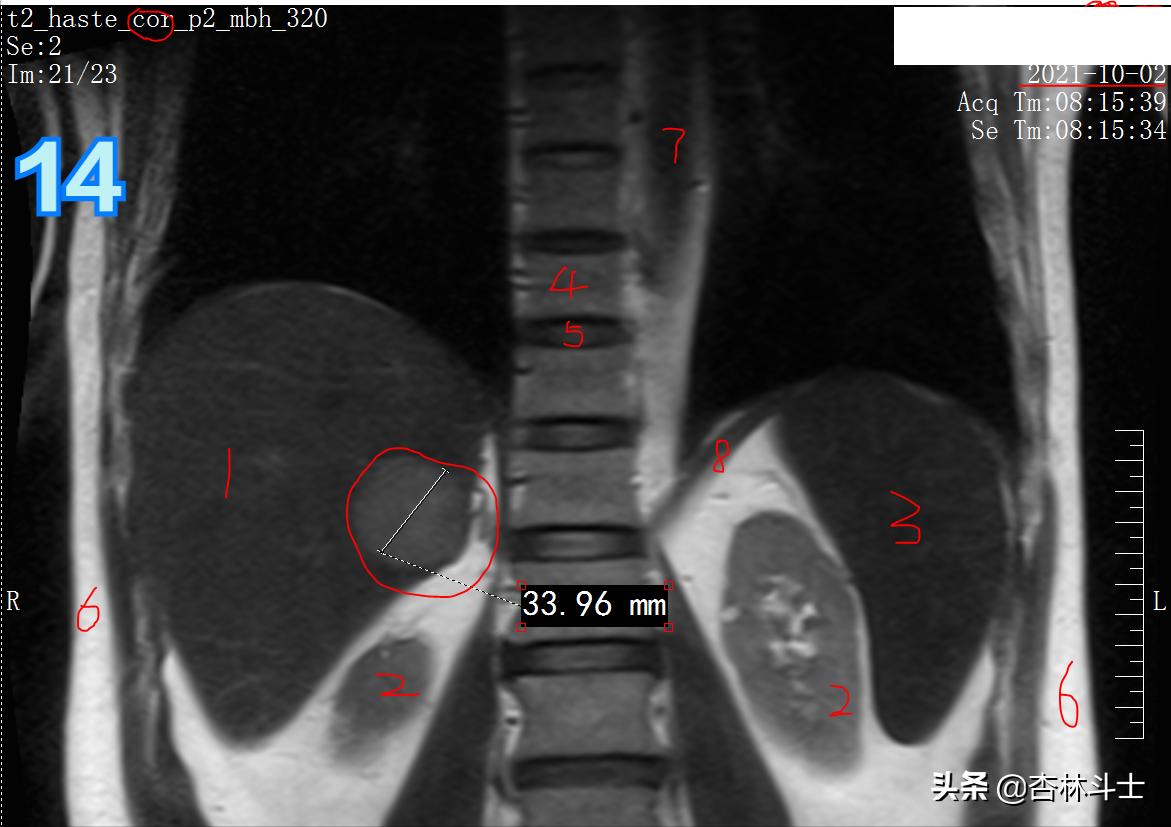

T2冠状位

图14中 1、肝脏 2、双肾 3、脾 4、胸椎椎体 5、椎间盘 6、皮下脂肪 7、胸主动脉 8、膈肌